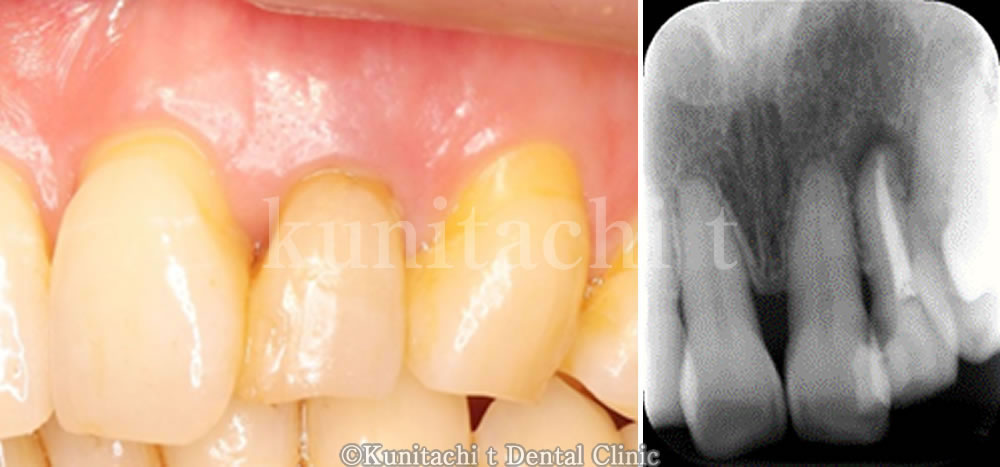

▼他院にて抜歯を宣告された歯を精密根管治療にて保存した症例をご紹介します。

部位は右下の6番目の歯で、レントゲンでみてみると黒い透過像が確認できます。患者さん本人には違和感や鈍痛が認められる状態でした。

過去に根管治療を行った歯であり、何らかの影響で再感染を起こしてしまっている状態です。患者さんと相談した上で再根管治療を行い、抜歯を回避し保存できるかトライしてみることにしました。

根管充填後のレントゲン写真と土台(コア)築造後のレントゲン写真になります。

現在、仮歯にて経過観察中ですが、特に大きな症状もないとのことです。ここまでの治療で今回は治療回数でいくと4回でした。今後、問題なければ最終的な適合の良い被せ物(クラウン)を入れていく予定です。この症例のように、一見残すことが難しいと思われる歯もケースによっては保存できる可能性があります。